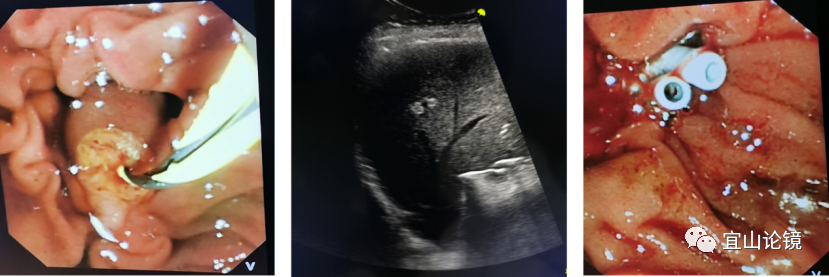

患者老年男性,因寒战、上腹痛急诊入院,入院后积极完善相关检查,经多学科会诊后诊断为“急性梗阻性化脓性胆管炎、感染性休克“,病情危急。经过多学科会诊讨论专家们一致认为,应尽早进行ERCP手术抢救病人,但当时病人情况危急,已无法转运至内镜中心ERCP手术室,只能行急诊床旁ERCP。床旁ERCP由于没有X线的指引,完全凭借操作医生的手感和经验进行盲插管,操作难度大,加之病人高龄,又增加了手术难度。生死瞬间,医生们只能放手一搏,消化内镜中心宛新建主任带领ERCP团队,凭借多年的临床经验,决定在床旁B超辅助下行ERCP术。

术中患者取仰卧位,给予心电监护,于床边行十二指肠镜操作,通过食管、胃腔后快速进入十二指肠。

确认乳头后,在床旁B超辅助下行插管,插管成功后退出导丝,顺导丝孔道以空针抽吸见脓性胆汁流出,再次床旁B超确认导丝位置后,置入塑料胆管支架于胆管内,定位引流通畅,再次床旁B超确认支架在位引流通畅,遂结束操作。